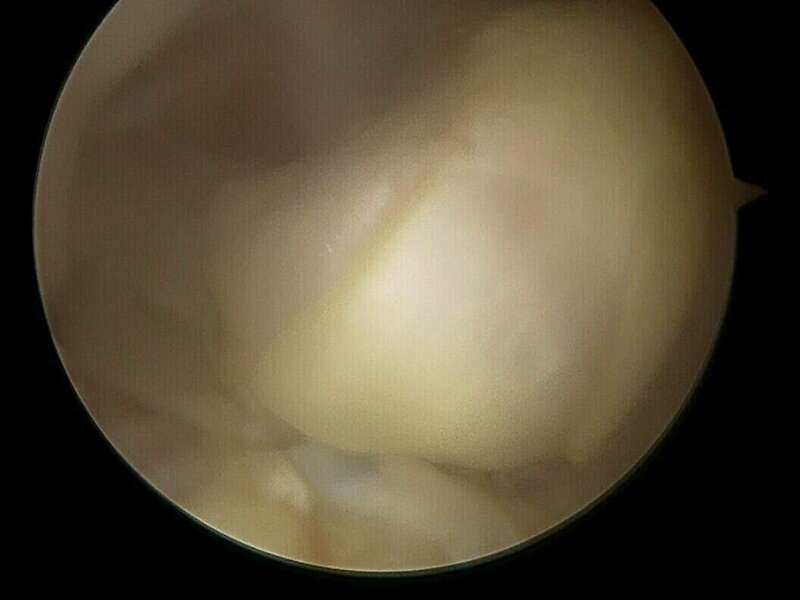

En l’absence d’évolution spontanément favorable, le traitement est systématiquement chirurgical et consiste à retirer ce nodule d’arthro-fibrose sous arthroscopie au cours d’une hospitalisation de courte durée en Chirurgie Ambulatoire. Lors de l’intervention chirurgicale, le chirurgien s’assurera de la récupération de l’extension complète du genou.

Galerie photo